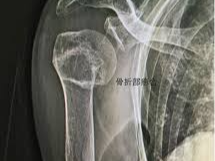

어깨뼈 골절은 어깨 주변을 구성하는 여러 뼈 중 하나가 부러지는 상태를 의미합니다. 어깨는 단순한 관절이 아니라 여러 뼈와 인대, 근육이 복합적으로 연결된 구조이기 때문에 골절의 종류도 다양하게 나타납니다. 흔히 발생하는 골절 위치는 견갑골, 쇄골, 상완골 근위부입니다. 특히 낙상 사고나 교통사고에서는 상완골 근위부 골절이 자주 발생합니다.

이 중에서도 상완골 근위부 골절은 고령자 낙상 사고에서 매우 흔하게 나타나는 골절이며, 경우에 따라 금속 핀이나 금속 플레이트를 이용한 고정 수술이 필요할 수 있습니다.

- 초기 진단

- X-ray 촬영

- CT 검사

- 골절 위치 확인